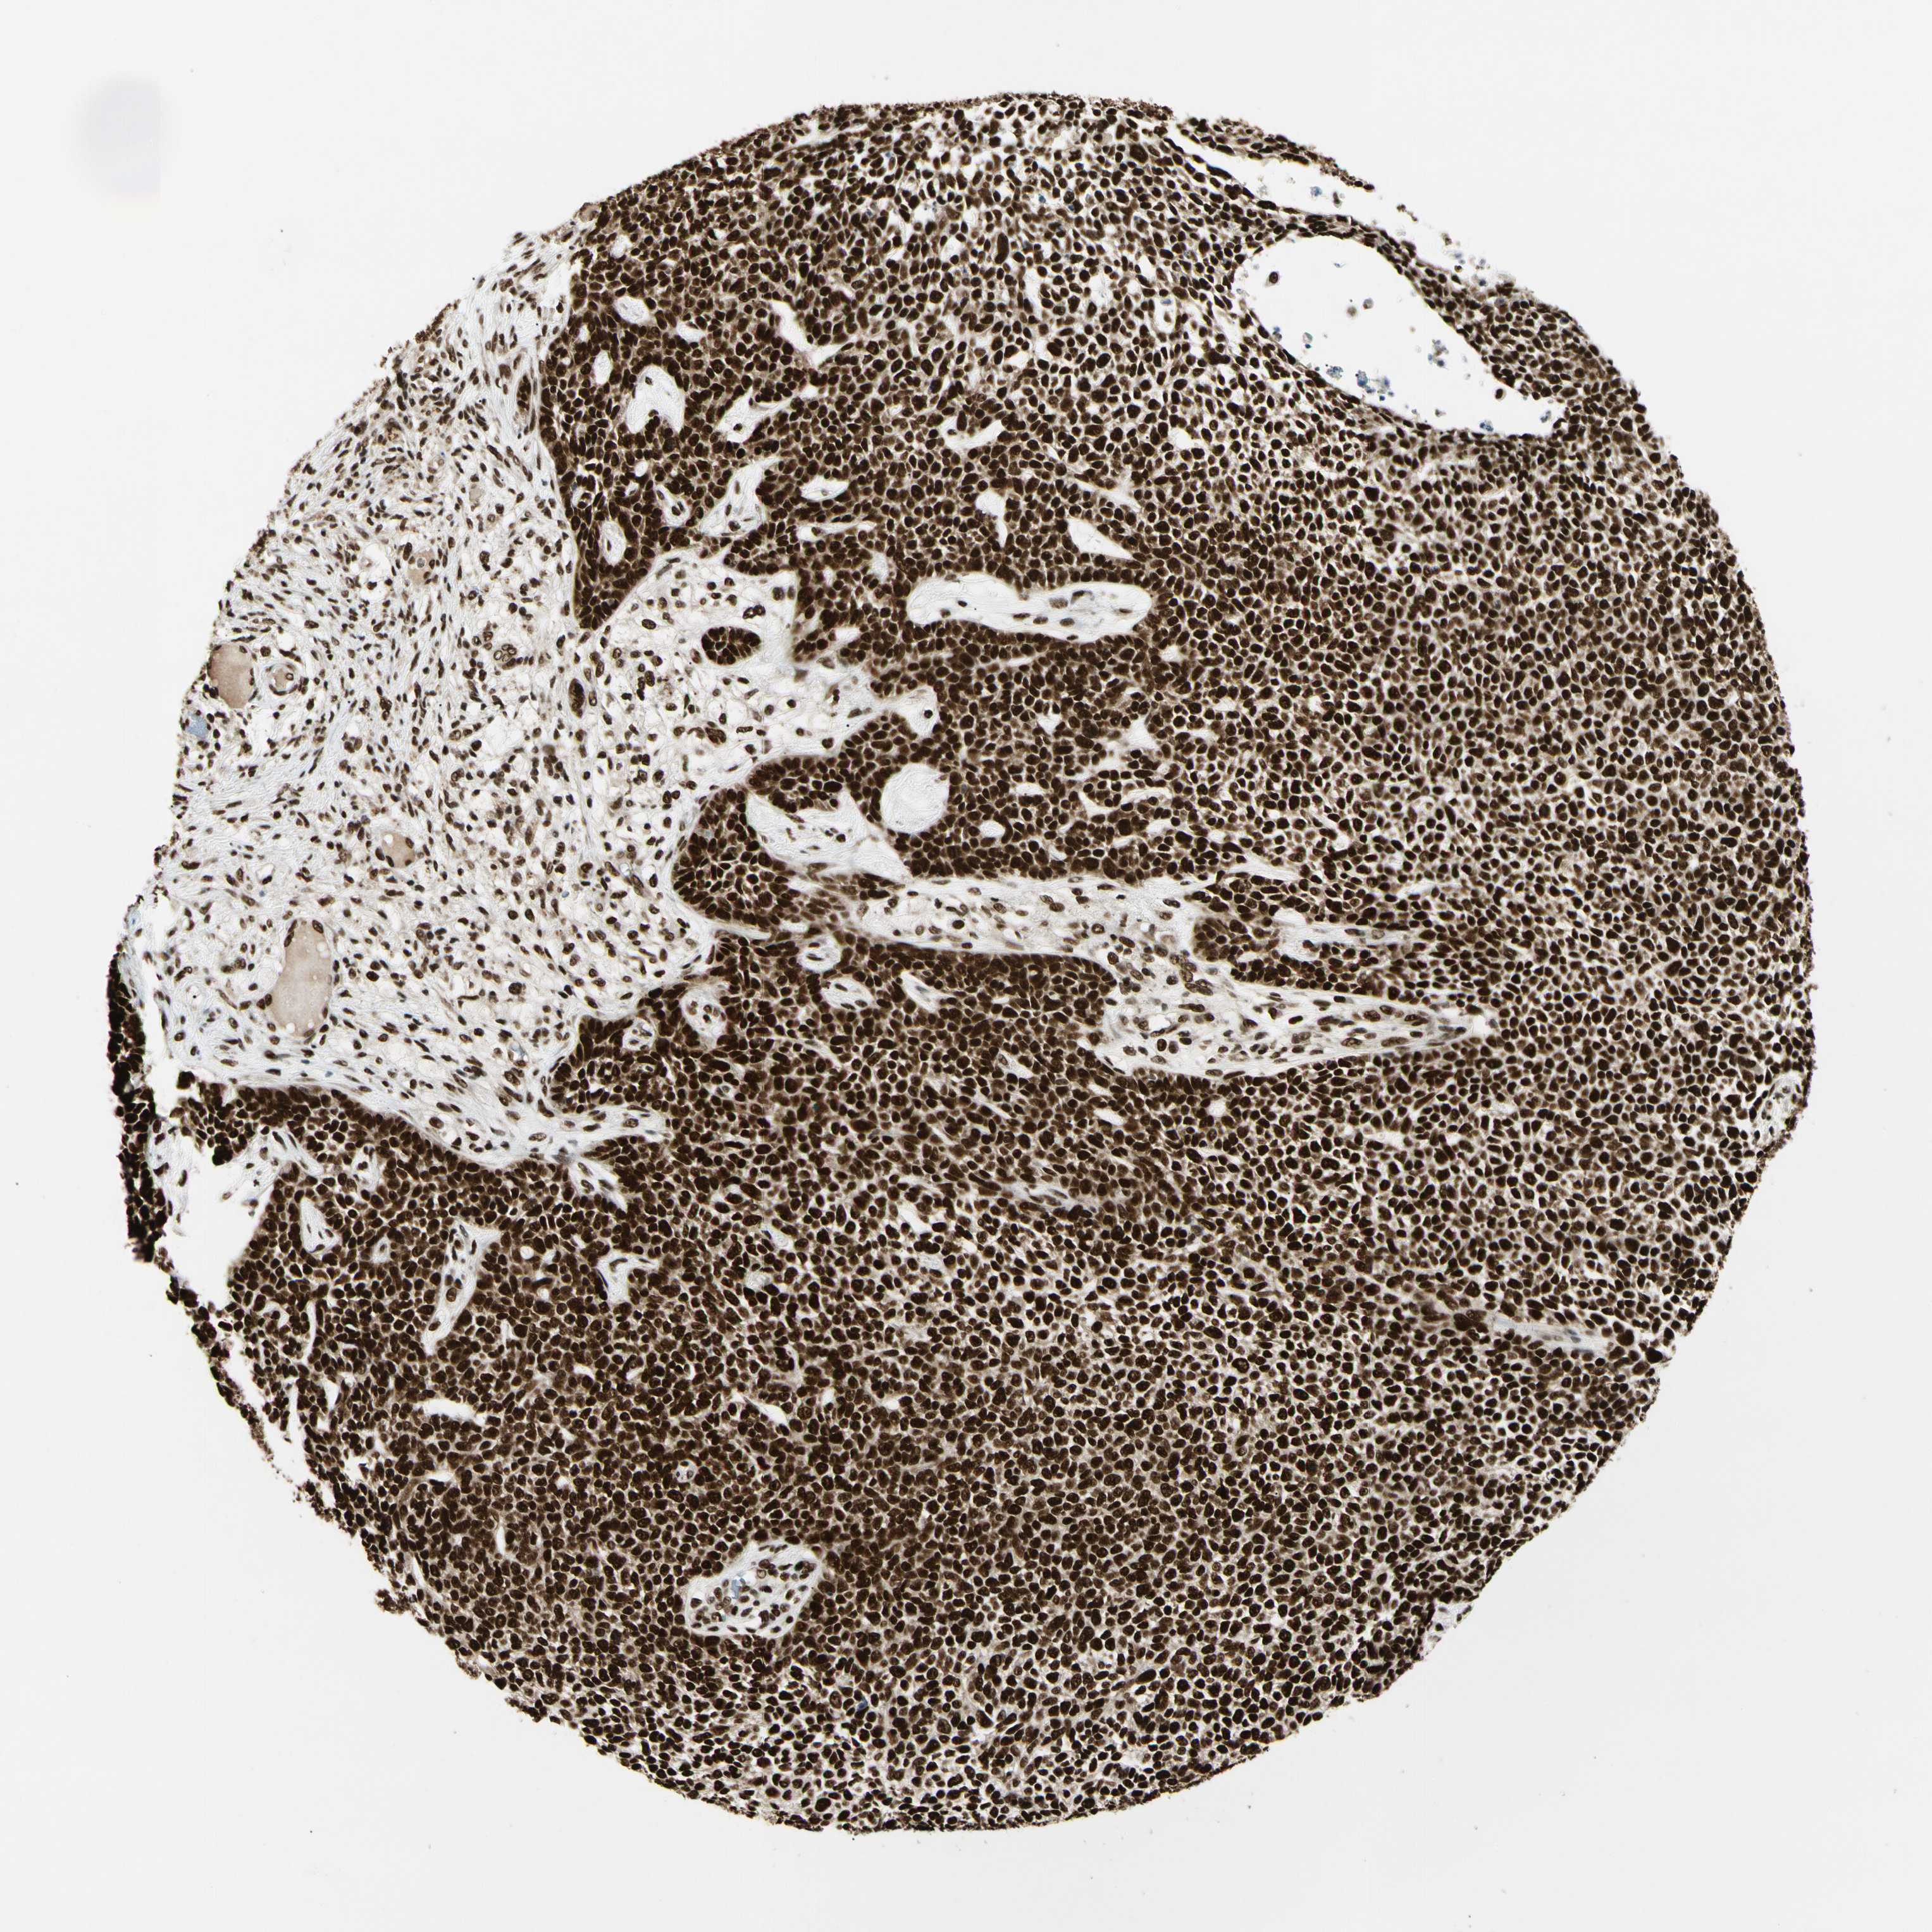

SKIN CANCER - Protein expressioni

A mouse-over function shows sample information and annotation data. Click on an image to view it in a full screen mode. Samples can be filtered based on level of antibody staining by selecting one or several of the following categories: high, medium, low and not detected. The assay and annotation is described here.

Antibody staining in the annotated cell types in the current human tissue is reported as not detected, low, medium, or high, based on conventional immunohistochemistry profiling in selected tissues. This score is based on the combination of the staining intensity and fraction of stained cells.

Each image is clickable and will lead to virtual microscopy that enables deeper exploration of all samples and also displays staining intensity scores, fraction scores and subcellular localization as well as patient and tissue information for each sample.

Antibody CAB033036

Staining

High

Intensity

Strong

Quantity

Location

Squamous cell carcinoma, NOS